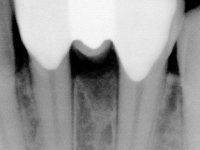

DIAGNOSIS:

Female patient, 40 years old, non-smoker. Presented agenesis of tooth 31 with the presence of deciduous tooth 71.

After clinical and radiographic examination, two alternatives for the oral rehabilitation were proposed: